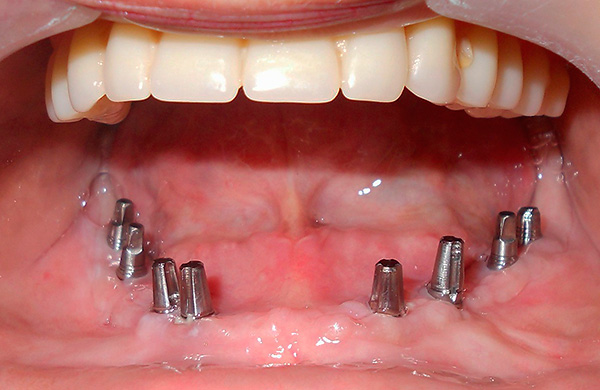

Na próxima etapa do implante basal, a instalação real dos implantes é realizada pelo método de punção ou incisão (ou imediatamente após a extração do dente). Uma punção torna possível realizar todo o procedimento sem suturar e é adequada para pessoas com gengivas enfraquecidas e inflamadas.

Nota

Com base nos dados simulados, modelos cirúrgicos individuais são desenvolvidos usando impressoras 3D. Geralmente, são estênceis de silicone sobrepostos na crista alveolar durante a cirurgia. Eles têm aberturas com um certo ângulo de inclinação através do qual os implantes são inseridos no osso.Assim, eles são instalados em um local precisamente calibrado, o que torna a operação menos arriscada e menos traumática.

O último estágio do implante basal é a prótese. Após a instalação dos implantes basais, a prótese é geralmente colocada por 2-3 dias - para criar a carga primária necessária. A prótese é feita com moldes removidos da mandíbula do paciente. Ao mesmo tempo, todos os implantes instalados são impressos na impressão, cuja relação espacial já é estudada pelo técnico em odontologia nos modelos obtidos, que faz a prótese necessária no laboratório odontológico (ao mesmo tempo, são levados em consideração os dados do modelo de computador criado na fase preliminar).